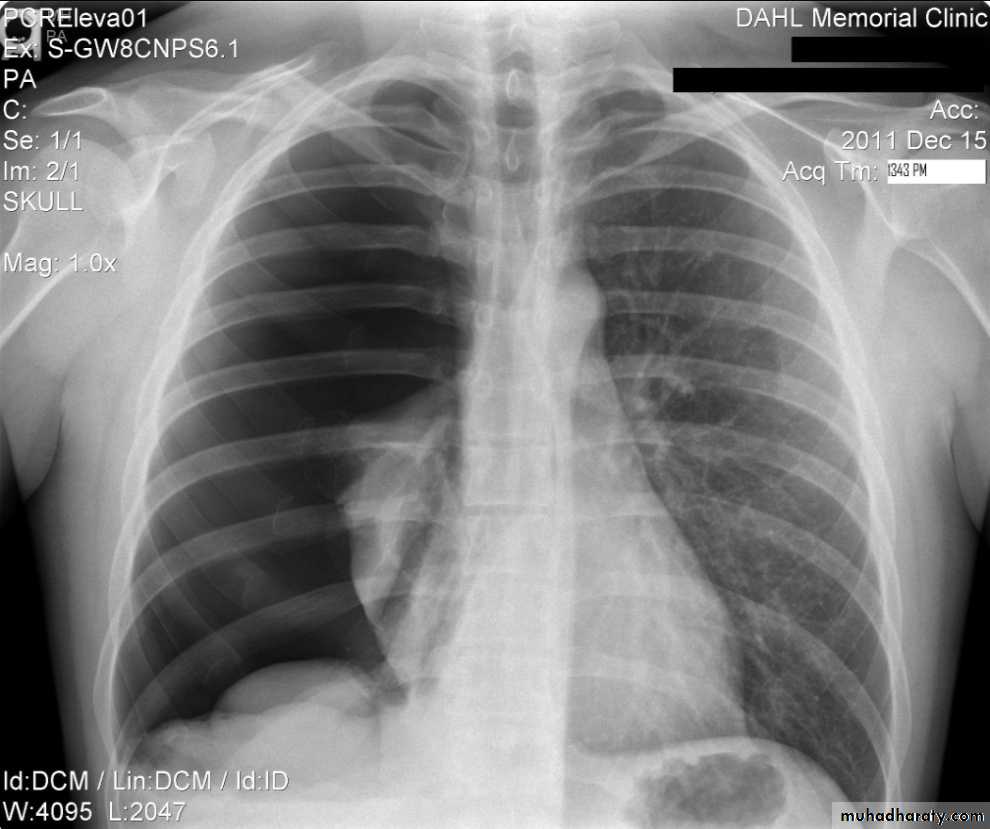

Left upper lobe collapse has distinctive features but can be challenging to identify on chest radiographs by the uninitiated.

Radiographic features

The left upper lobe collapses anteriorly becoming a thin sheet of tissue apposed to the anterior chest wall, and appears as a hazy or veiling opacity extending out from the hilum and fading out inferiorly . It thus reverses the normal slight increase in radiographic density seen as you move down the lung (due to increased thickness of the chest soft tissues).

Parts of the normal cardiomediastinal contour may also be obliterated where the left upper lobe, particularly the lingula abut the left heart border. The anterior parts of the aortic arch are also often obliterated from view.

In some cases the hyperexpanded superior segment of the left lower lobe insinuates itself between the left upper lobe and the superior mediastinum, sharply silhouetting the aortic arch and resulting in a lucency medially. This is known as the luftsichel sign.

The left hilum is also drawn upwards, resulting in an almost horizontal course of the left main bronchus and vertical course of the left lower lobe bronchus.

Non-specific signs indicating left sided atelectasis will also be present, including:

elevation of the hemidiaphragm

'peaked' or 'tented' hemidiaphragm: juxtaphrenic peak sign

crowding of the left sided ribs

shift of the mediastinum to the left

On lateral projections the left lower lobe is hyperexpanded and the oblique fissure displaced anteriorly. There is associated increase in the retrosternal opacity.